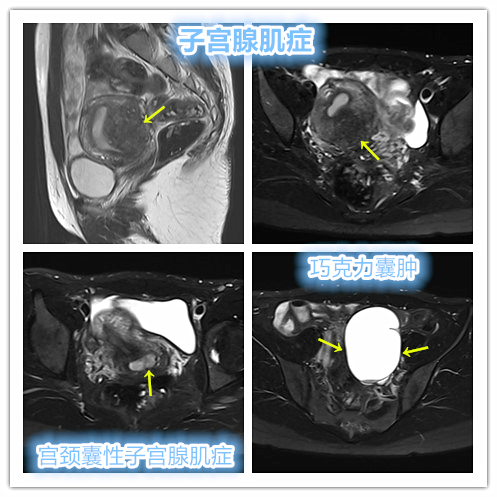

囊性子宫腺肌症是子宫腺肌症的一种特殊类型,类似子宫腺肌瘤。囊性子宫腺肌症病理特点为子宫中内衬子宫内膜和外周包围子宫平滑肌组织的囊性结构,囊腔内含陈旧血液的囊液,一般囊腔10~20mm,又称子宫腺肌症囊肿或囊性子宫腺肌瘤。

发病年龄在13~55岁,患者中年龄≤30岁的约占65%~75%。按临床特征可分为青少年型与成年型。虽然囊性子宫腺肌症在成年妇女较为少见,但却可以出现在年轻妇女特别是青春期女孩,患者常有明显痛经症状。

典型病例

例1

年轻女性,痛经10多年,磁共振检查显示子宫腺肌症,宫颈部囊性子宫腺肌症及左侧巧克力囊肿。